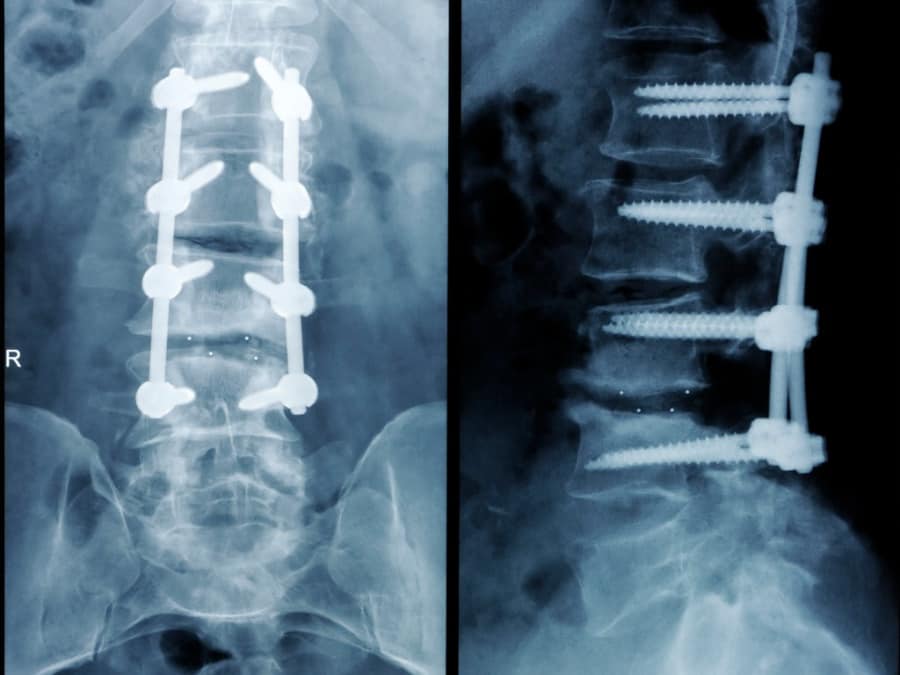

當醫師到現在第一次看到腰椎第一節到第五節全部上鋼釘融合的患者,開過四次刀後仍然覺得下背嚴重疼痛,已經伴隨雙腳走路無力,幫她開刀的主任已經拒絕再度幫她開第五次刀了!!因為沒空間可以開了,這是很典型的” 腰椎術後疼痛症候群” – FBSS。